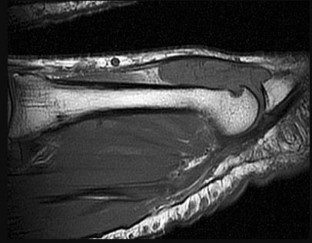

Surgical repair of the injury shown in the MRI scans in Figures 1 through 4 through a single-incision approach has a higher incidence of

The MRI scans show a distal biceps tendon avulsion with significant retraction. When addressing these injuries, a single-incision approach has been associated with an increased risk of lateral antebrachial cutaneous nerve injury. A two-incision approach has been associated with an increased risk of heterotopic ossification, second surgeries and posterior interosseous nerve injury.